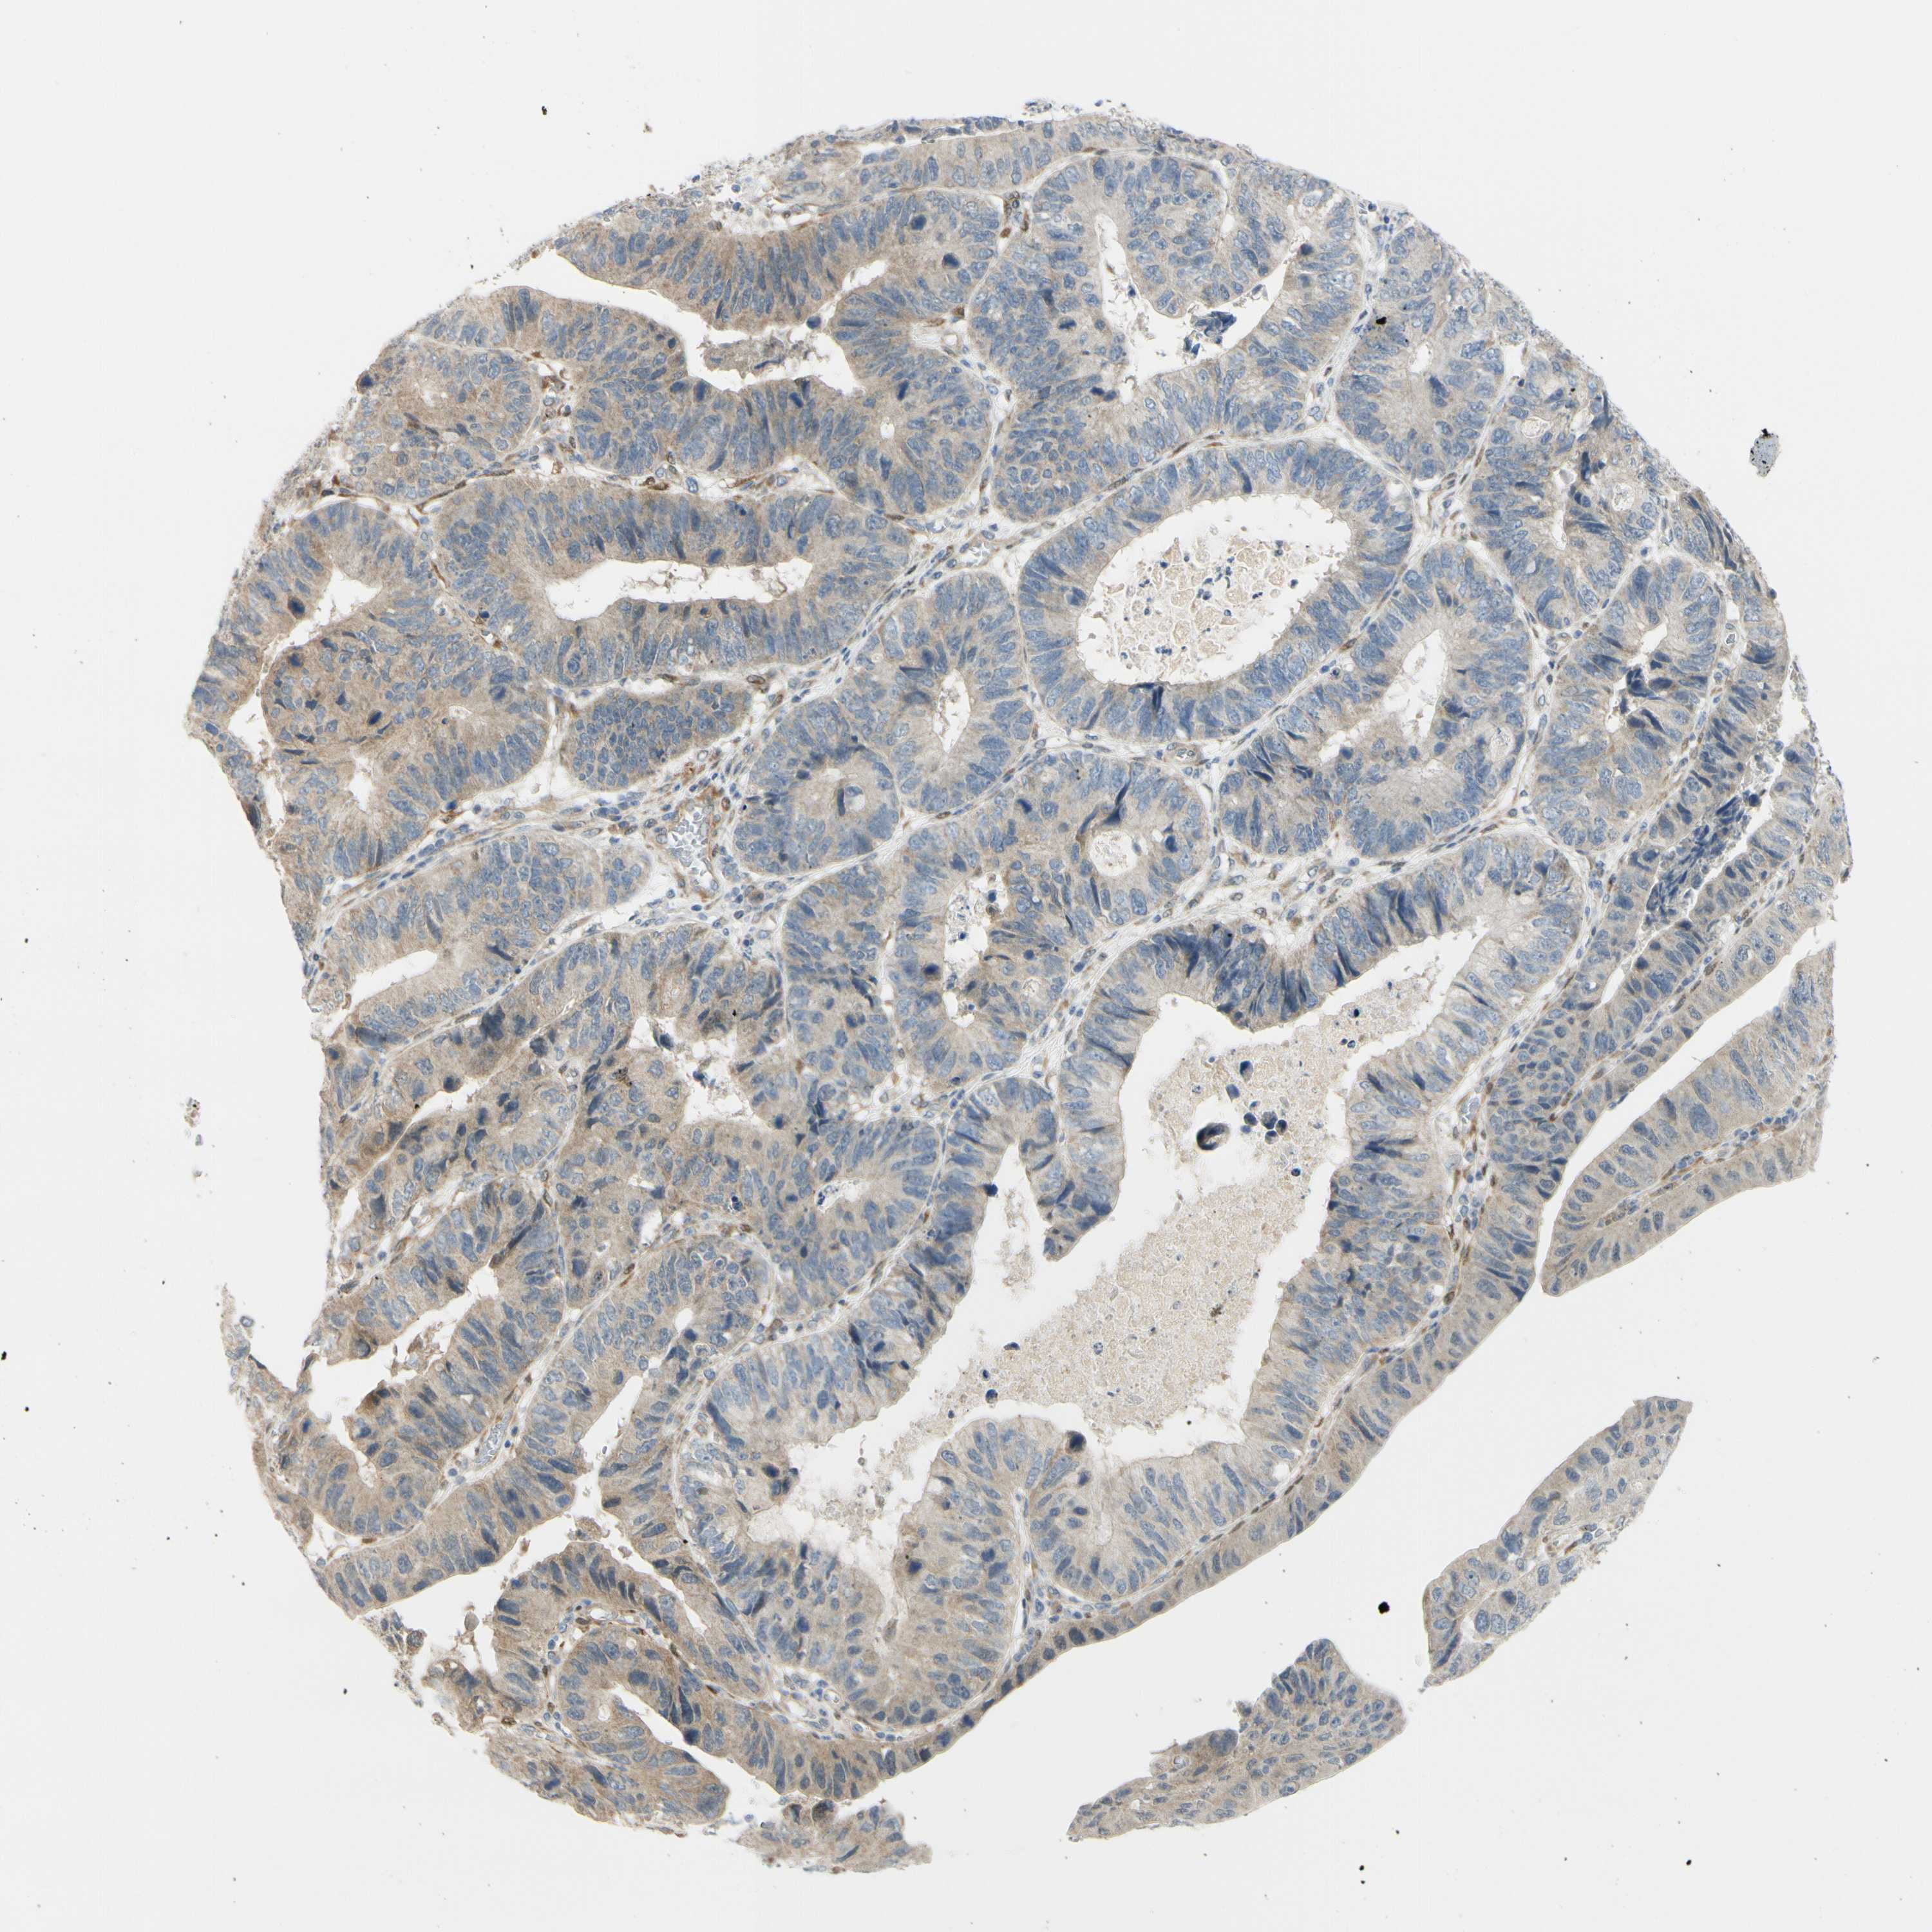

STOMACH CANCER - Protein expressioni

A mouse-over function shows sample information and annotation data. Click on an image to view it in a full screen mode. Samples can be filtered based on level of antibody staining by selecting one or several of the following categories: high, medium, low and not detected. The assay and annotation is described here.

Antibody stainingi

Antibody staining in the annotated cell types in the current human tissue is reported as not detected, low, medium, or high, based on conventional immunohistochemistry profiling in selected tissues. This score is based on the combination of the staining intensity and fraction of stained cells.

Each image is clickable and will lead to virtual microscopy that enables deeper exploration of all samples and also displays staining intensity scores, fraction scores and subcellular localization as well as patient and tissue information for each sample.

Antibody HPA005922

Antibody HPA006028

Antibody CAB008368

Staining

High

Medium

Low

Not detected

Intensity

Strong

Moderate

Weak

Negative

Quantity

>75%

75%-25%

<25%

None

Location

Nuclear

Cytoplasmic/membranous

Cytoplasmic/membranous,nuclear

Adenocarcinoma, NOS

Adenocarcinoma, High grade